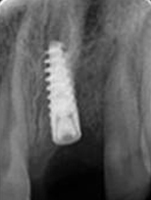

X-ray of Implant

Single Tooth Implant